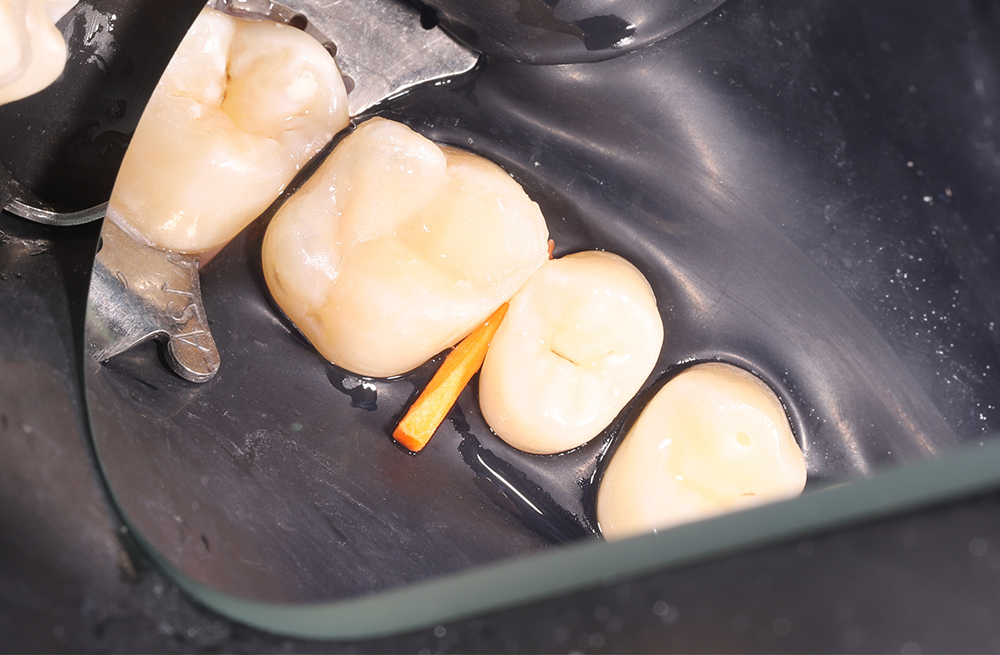

Устранение кариозного поражения зуба с применением коффердама и композитной реставрации

Препарирование и реставрация 36 зуба при вторичном кариесе с надежной изоляцией и полировкой пломбы